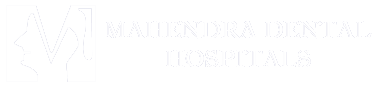

All on X implant systems include All on 4, All on 6 and All on 8 implant systems, which differ in how many screws are used per bridge. They are the best choice for patients who want to have the most affordable and very durable implant system for restoring many teeth at once. Patients who have more dense jaws and desire even better stability can choose All on 6 systems. More information about our All on X implant procedures, including All on 4 dental implants.

All on 4 implant systems have four screws per bridge and are among the most popular options at our clinic. Their cost is the lowest among all All on X systems.

All on 8 implant system are used when the greatest stability is required to support the fixed bridge.

3 on 6 implant system are a type of implant system which consists of three fixed bridges, each supported by two implant screws.